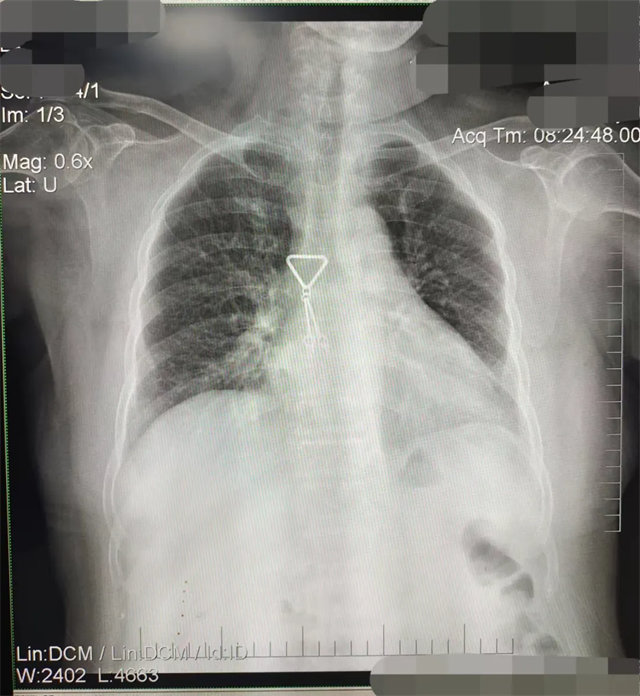

缺陷:双侧胸锁关节不对称,且有手机显影。

解决:去除手机后,使患者左侧紧贴成像件曝光。